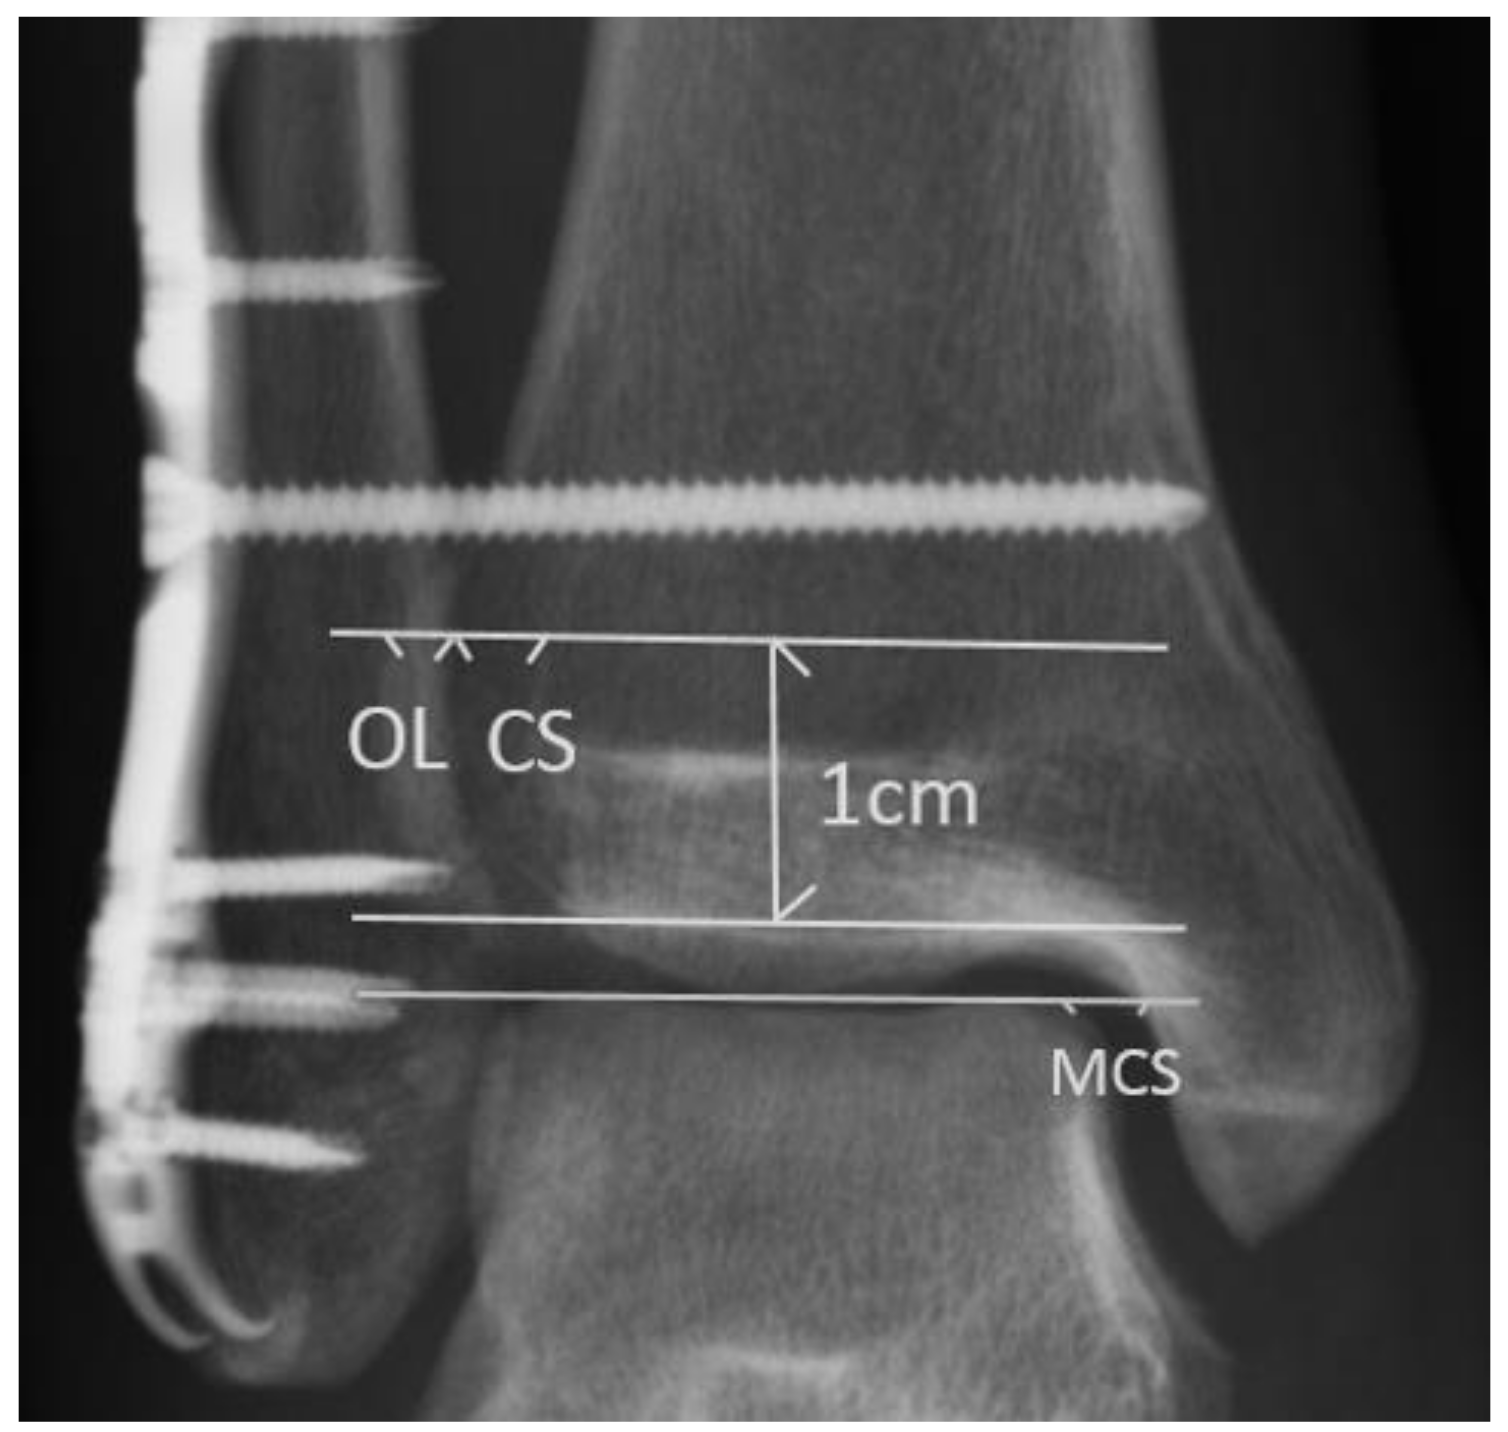

Data analysis of CS, OL, and MCS in anteroposterior radiographs was conducted at three time points: after syndesmotic fixation (post-SF), before syndesmotic screw removal (pre-SR), and at the last follow-up (last-FU). The post-SF radiographs were obtained immediately after syndesmotic fixation. The pre-SR radiographs were obtained immediately before the syndesmotic screws were removed. The last-FU radiographs were the most recent follow-up radiographs that could be obtained after the syndesmotic screws were removed. To compare the difference among the radiographic outcomes at each time point, three periods of interest were defined. The total observation period was defined as the period from the post-SF time point to the last-FU time point. The pre-SR period was defined as the period from the post-SF time point to the pre-SR time point and was equal to the duration of syndesmotic screw retention. The post-SR period was defined as the period from the pre-SR time point to the last-FU time point (Figure 2).

Figure 2. Demonstration of serial images evaluation: (a) Patients who met the inclusion criteria were collected; (b) pre-SR anteroposterior radiographs were obtained; (c) last-FU anteroposterior radiographs were obtained. CS: tibiofibular clear space; last-FU: last follow-up; OL: tibiofibular overlap; pre-SR: presyndesmotic screw removal.